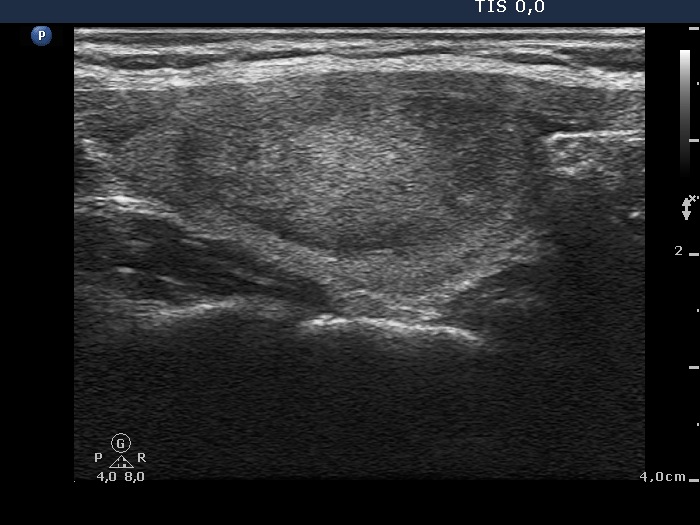

Ultrasonography: the thyroids were echonormal. There was a moderately hypoechogenic-echonormal nodule in the left lobe. The nodule displayed a halo sign but neither perinodular nor intranodular blood flow.